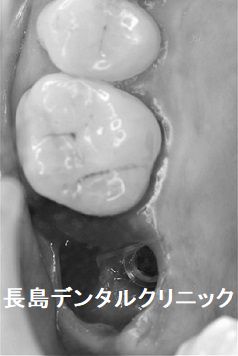

1,インプラント埋入前

他院のご紹介で来院された患者様です。右上奥歯が噛むと痛いので、

CT検査を依頼されました。(黄色い矢印の部分)視診では治療を受

けた形跡や虫歯はなく歯茎に発赤や腫脹もありませんが、CT検査を

したところ、歯を支えている顎の骨が吸収を起こし保存が不可能な

状況でした。抜歯を行う前に、患者様と抜歯後の治療計画を相談した

ところ、インプラントを希望されました。

2、抜歯とインプラント即時埋入

歯を支えている顎の骨は吸収していましたが、それでも抜歯即時埋入が

十分可能な骨の量があることを、術前のインプラントシュミレーション

で確認できましたので、抜歯窩を十分に搔爬しインプラントを埋入しま

した。